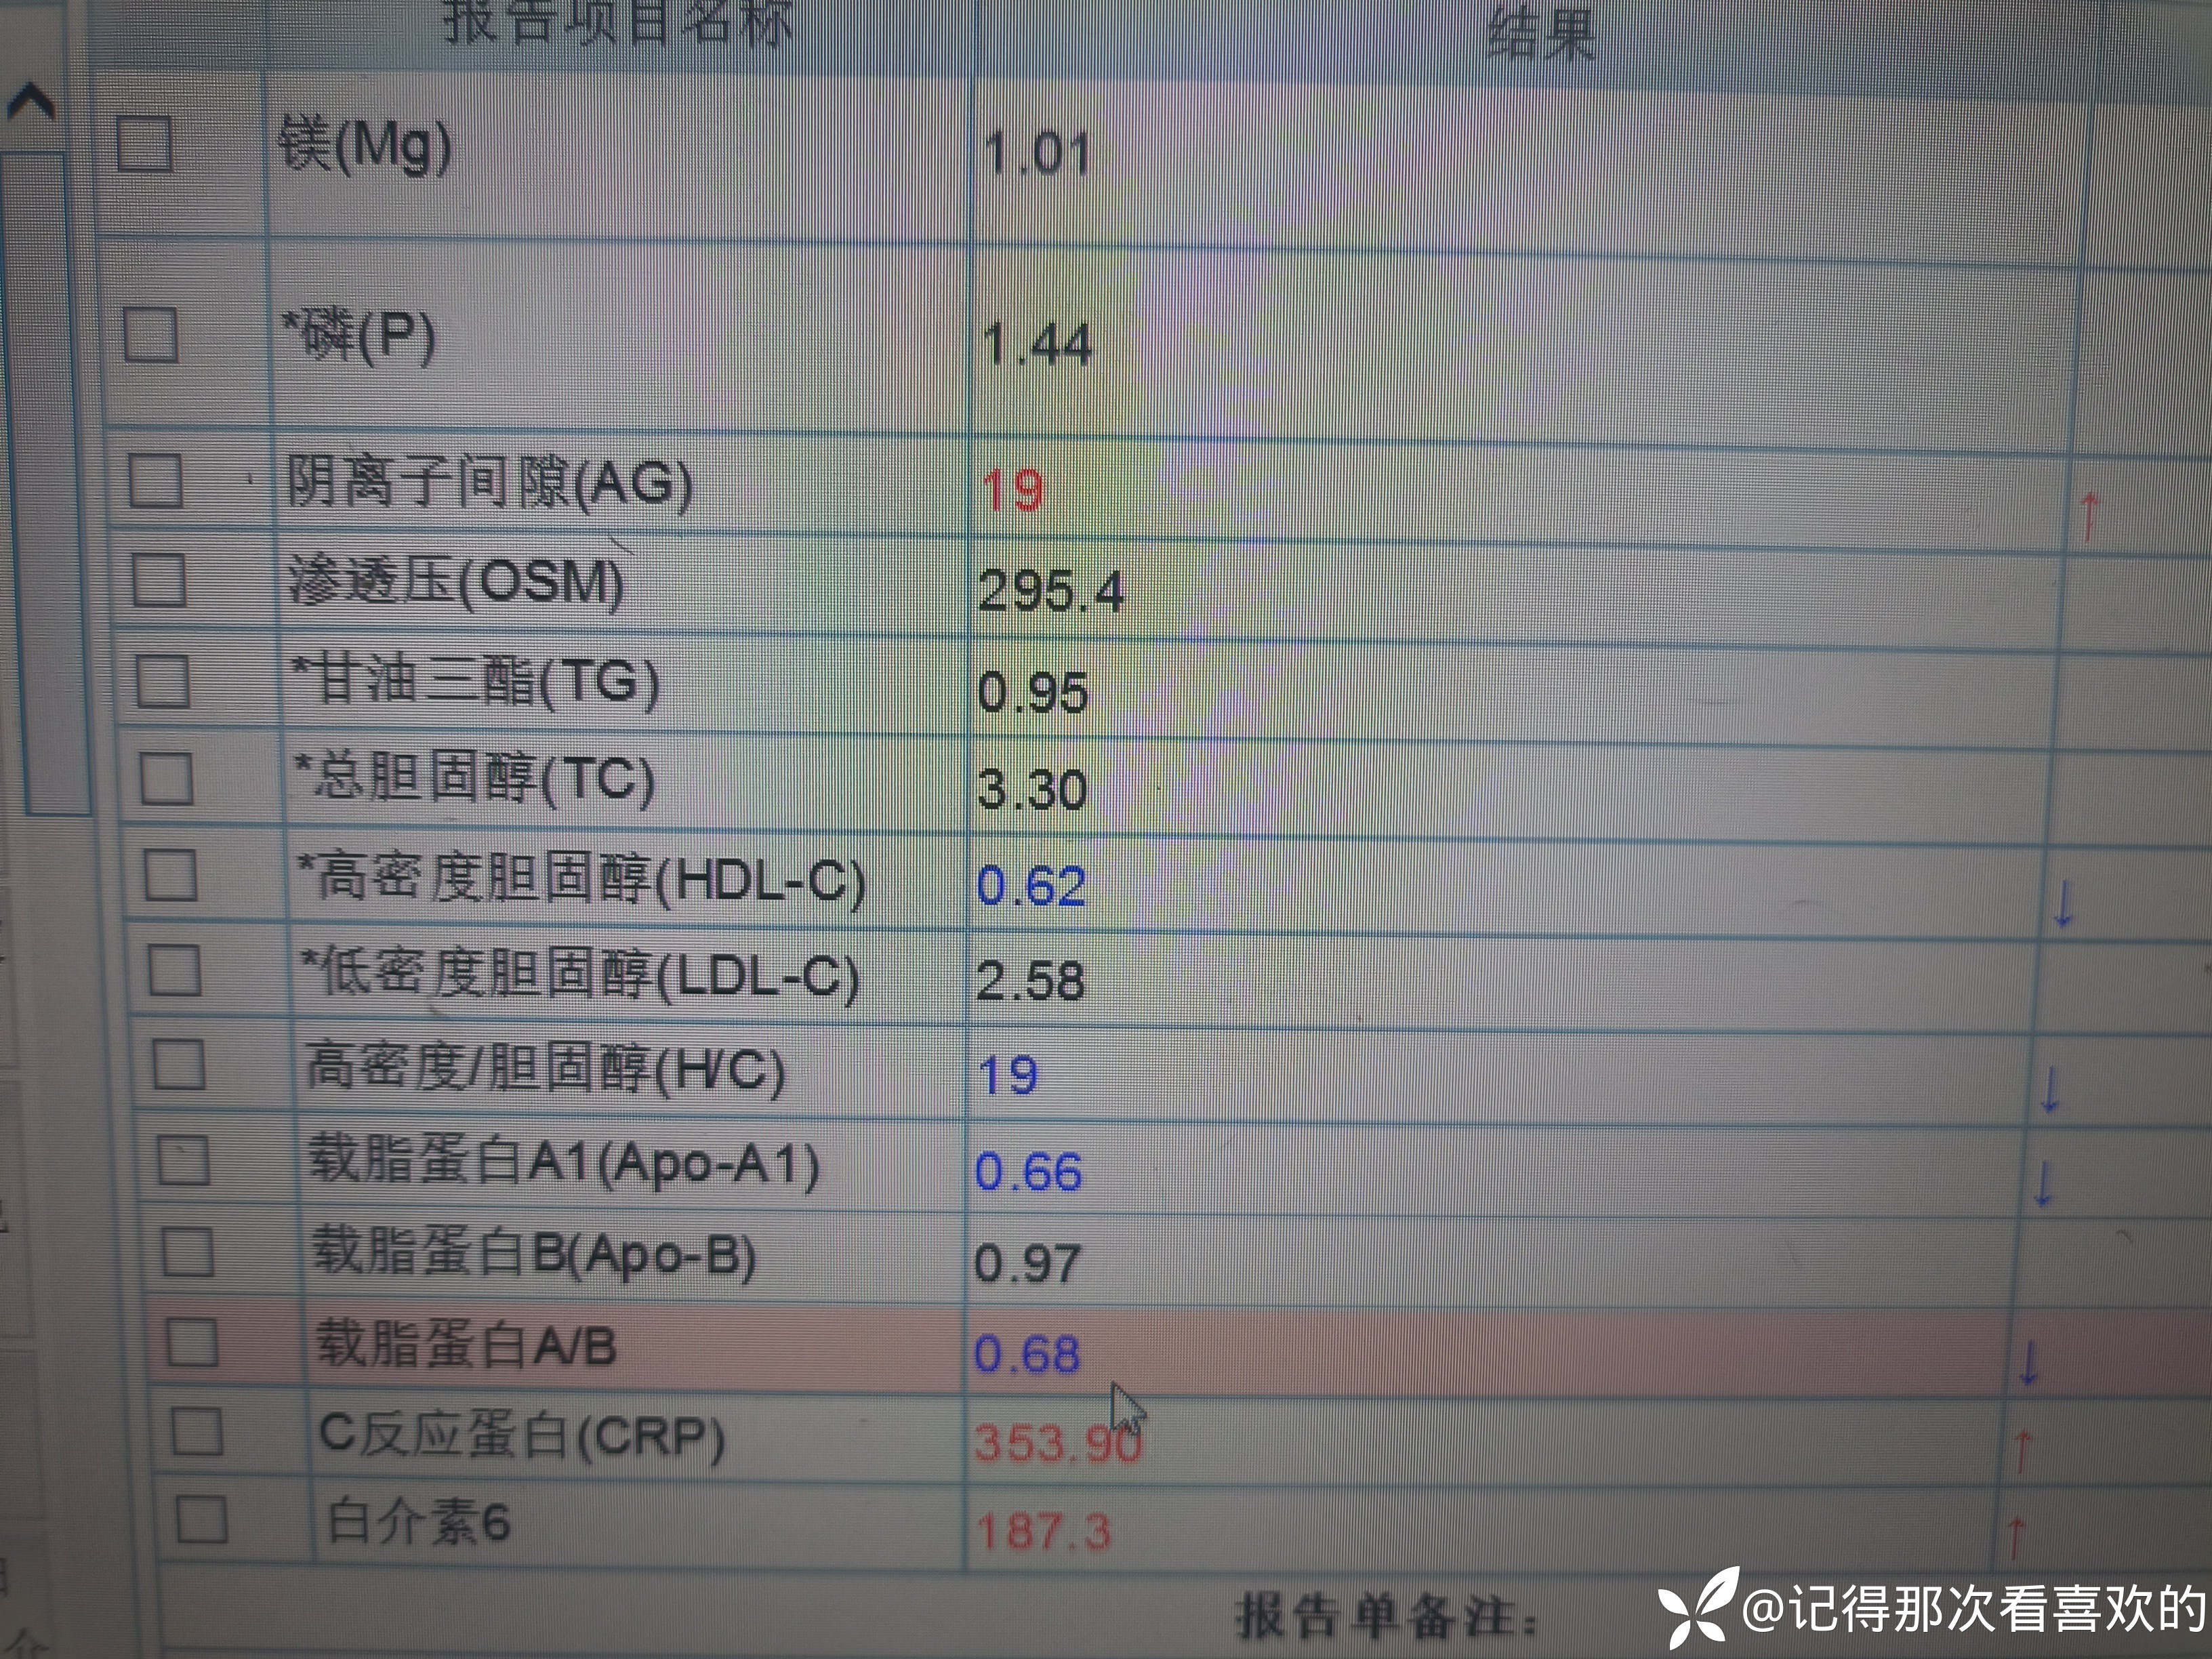

病例特点:患者钟某 男,14岁,以"髋、膝、足肿痛1年余,加重3日。"为主诉入院。现病史:缘于1年前无明显诱因出现左侧髋关节、双足跟、左踝关节、右足第一足趾关节肿胀、疼痛, 疼痛呈持续性,多于阴雨天、活动后症状加重,疼痛未向他处放射、转移,症状严重时行走困难。遂就诊于我科,查"HLA-B27(+)、CRP 70mg/L、骶髂MR:骶髂关节肿胀",诊断为"强直性脊柱炎",先后予皮下注射"司库其尤单抗150mg qw、阿达木单抗40mg q2w",上述症状较前好转,此后不规律用药,于半年前自行停用上述药物,未再规律随诊。3日前再发左膝、双肘关节肿痛,性质同前,程度较前加重,影响行走,伴有发热,体温最高达39℃,自行服用退烧药(具体不详)后体温较前下降,上述关节肿痛无明显改善。现为求进一步治疗,就诊我院,门诊拟"强直性脊柱炎"收住入院。体格检查:T36.6℃ P138次/分 R50次/分BP/120/68mmHg 专科情况:生命征平稳,神志清楚,双肺呼吸音清,未闻及干湿啰音,心律齐,各瓣膜听诊区未闻及杂音,全腹软,无压痛及反跳痛,未触及包块,双肘、左膝关节肿胀、压痛、触之皮温高。双下肢无浮肿,病理征未引出。

诊疗计划:1.入院予二级护理,监测血压、脉搏、呼吸。2.入院完善三大常规、凝血、生化、骶髂MR、彩超、CT、心电图等相关检查评估病情。3.治疗上暂予抗炎镇痛,辅以护胃治疗,待相关检查结果回报后进一步治疗,本次就诊拟行生物制剂治疗,予完善骨保护药物,传染病相关检查排除禁忌症,患者本次发病伴有发热达39℃,追问病史患者诉偶有干咳不适,目前已改善,予完善呼吸道病原学检查明确病情。4.患者Padua评分1分,属于发生VTE低危风险,实行VTE基本预防,动态评估Padua评分。5.已将目前病情及现有临床诊断以及存在疾病复杂性、个体的差异性、对治疗的反应不同、鉴于目前医学技术水平有限,和下一步相关诊疗详细充分告知患者家属,取得家属的理解并同意配合下一步诊疗及检查。6.NRS-2002评分3分,目前患者营养状态尚可,进食情况尚可,根据病情变化动态评估。